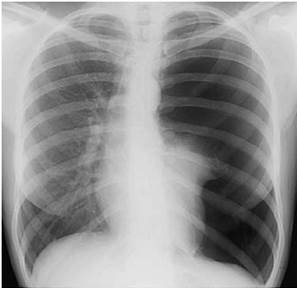

Больная 32 лет, жалуется на боль в левой половине грудной клетки, выраженную одышку с затруднением вдоха. Заболела внезапно, когда на фоне кашля появилась боль в левой половине грудной клетки, начала быстро нарастать одышка. Объективно: цианоз губ, левая половина грудной клетки несколько увеличена, отстает в акте дыхания, отмечается набухание шейных вен. При перкуссии: тимпанический оттенок звука слева, перкуторно нижняя граница левого легкого опущена (подвижность нижнего края не определялась из-за тяжести состояния больного). При аускультации отмечается резкое ослабление везикулярного дыхания. Назначена обзорная рентгенография органов грудной полости.

Для какой патологии характерна данная клиникорентгенологическая картина?

A) Пневмоторакс

$$$002

Больная 28 лет, заболела остро 1, 5 недели назад: температура тела повысилась до 38, 6, появился сухой кашель, сильная боль в левой половине грудной клетки на вдохе. Назначена обзорная рентгенография органов грудной полости.

Для какой патологии наиболее характерен данный рентгенологический

синдром?

A) Острая пневмония